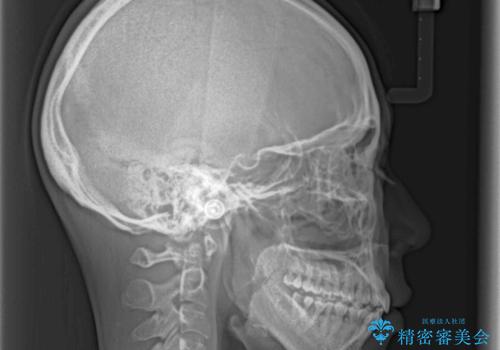

通常であれば、上下顎左右小臼歯各1歯の合計4本を抜歯しますが、歯肉退縮の著しい下顎前歯を抜歯して欲しいという患者様の強い希望により、上顎のみ左右小臼歯2歯を、下顎は前歯を1歯を抜歯することとしました。

抜歯する歯を変更したため奥歯の咬合はアンバランスとなりましたが、前歯は綺麗に整い、歯肉退縮も回避できました。